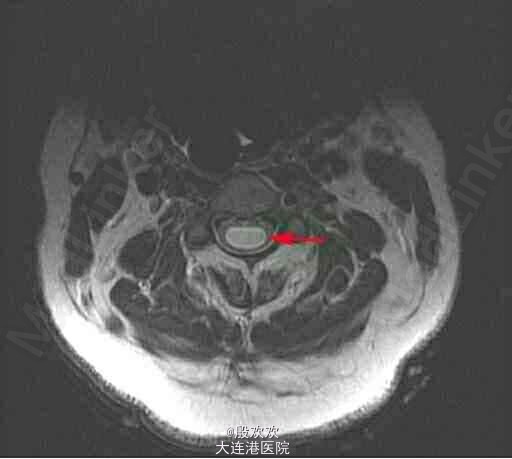

患者,女,51岁,因“右上肢无力萎缩10+年,双上肢麻木5年”入院。患者10+年前感右上肢力弱,逐渐加重,并发现右手肌肉渐萎缩。后双上肢麻木。

查体:生命体征平稳,双上肢皮肤粗糙。专科查体:神清,语利,双侧颈5-胸4水平痛温觉减退。双下肢肌张力稍高,右手骨间肌肉萎缩。双侧腹壁反射消失,双肱二头肌肌腱、肱三头肌肌腱、桡骨膜反射减低,双侧膝反射、踝反射明显增高。 辅助检查:头+颈椎+胸椎MRI:charis畸形并脊髓空洞症。

诊断:脊髓空洞症并小脑扁桃体下疝畸形:charis I型畸形。治疗:给于给于维生素B、ATP、肌苷等营养神经及康复治疗。